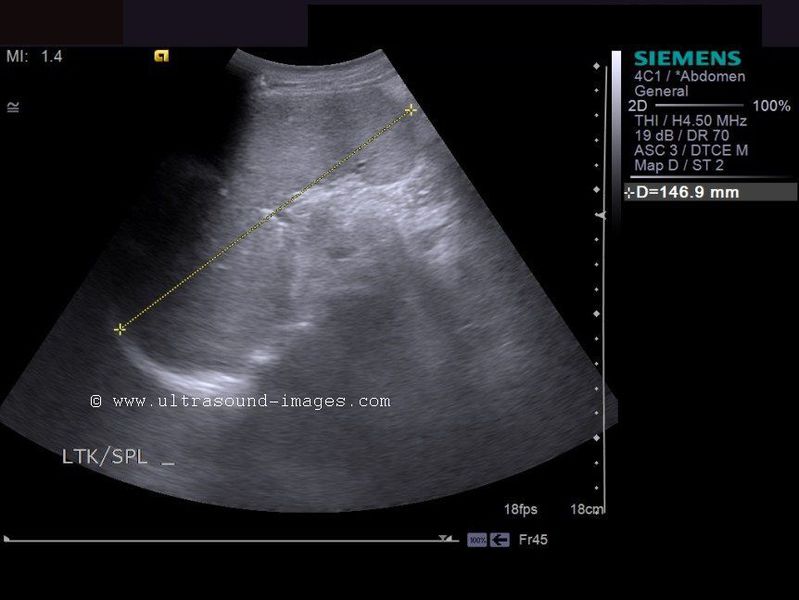

Elongated Left Lobe of Liver (the Beaver Tailed Liver)

Long left lobe of liver (normal variant).

In certain thin individuals (usually seen in thin women), the left lobe of liver appears elongated (see ultrasound images above), and overlies the spleen. In the above pictures, the spleen is seen to be hyperechoic compared to the left lobe (the so called "beaver tailed liver"). Ultrasound images courtesy of Dr. Ravi Kadasne, UAE. The machine used here is the Philips IU 22.